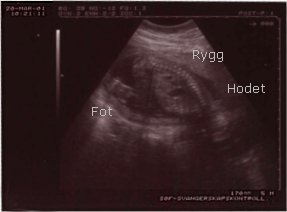

Ultralydsundersøkelse #2

Tirsdag 20.mars 2001 var det tid for ultralydsundersøkelse #2 på SØF. Jordmoren var den samme som sist. Mininurket hadde vokst som h*n skulle. Fikk satt termin til 18.aug. (Det er den terminen som kommer til å bli brukt resten av svangerskapet). Var da, i følge ul-terminen, i uke 18+5. Morkaken lå denne gangen ganske langt ned - så enten bommet jordmoren eller jeg forrige gang. Fikk ny time til ul tirsdag 29.mai. Skal da sjekke om jeg må ha keisersnitt eller om det går greit å føde normalt. Jordmoren visste ikke helt om de kom til å utføre vekstestimeringen på den samme ultralydsundersøkelsen, eller om jeg kom til å få en ny time noen uker senere.